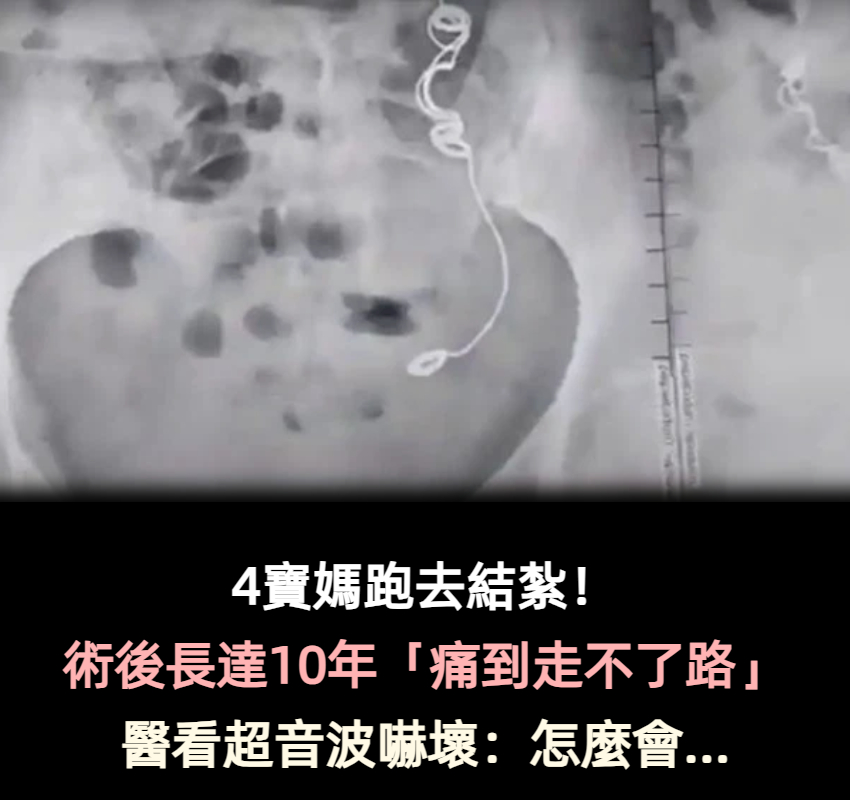

4寶媽跑去結紮!10年間「痛到走不了路」頻吃止痛藥 「超音波畫面曝光」醫生嚇壞:裡面有東西

圖/翻攝自 TVBS

心力交瘁的她幾乎想放棄自己,直到2022年11月有醫生驚覺不對勁,認為這些症狀都太詭異了,決定請她進行核磁共振與超音波檢查,這一查所有人都傻眼了,在她體內竟存在手術用的針線,在醫生詢問下她恍然大悟,是結紮手術害了她10年之久!

圖/翻攝自 mirror

艾德琳達崩潰表示:「我跟醫生都不敢相信眼前所見!」讓人傻眼的是,她去找當初幫她結紮的醫生,對方斬釘截鐵否認失誤,強調自己絕對不可能出現這樣的醫療疏失,還暗指是她自己將針線吞下肚。